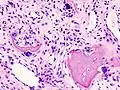

X-ray of erosive osteoarthritis of the fingers, also zooming in on two joints with the typical "gull-wing" appearance

Both primary generalized nodal osteoarthritis and erosive osteoarthritis (EOA, also called inflammatory osteoarthritis) are subsets of primary osteoarthritis. EOA is a much less common and more aggressive inflammatory form of osteoarthritis, which often affects the distal interphalangeal joints of the hand and has characteristic articular erosive changes on X-ray.[60]